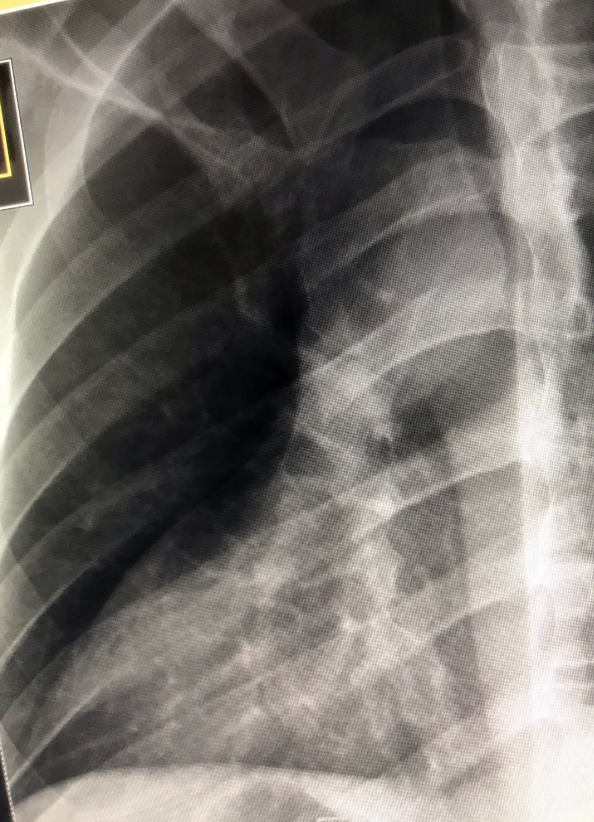

안녕하세요, 오늘은 복장뼈(흉골, sternum) 촬영방법 중 하나인 sternum oblique/RAO 촬영법에 대해서 설명하겠습니다. 흉골의 병리학적 상태 혹은 외상에 의한 골절이나 손상을 전체적으로 확인하는데 유용한 검사입니다. 특히 심장 음영에 겹쳐 관찰하는 특징이 있어 RAO방법이 주로 이용됩니다. 그럼 이미지와 함께 설명을 시작하겠습니다.

- 흉골체(body of sternum) 부터 검상돌기(xiphoid process) 까지 포함되도록 한다.

- 흉골이 심장 음영안에 보여야 한다.

- 흉골의 움직임으로 인한 흔들림이 적어야 한다.